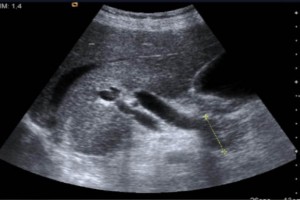

Diplomados en Ultrasonografía